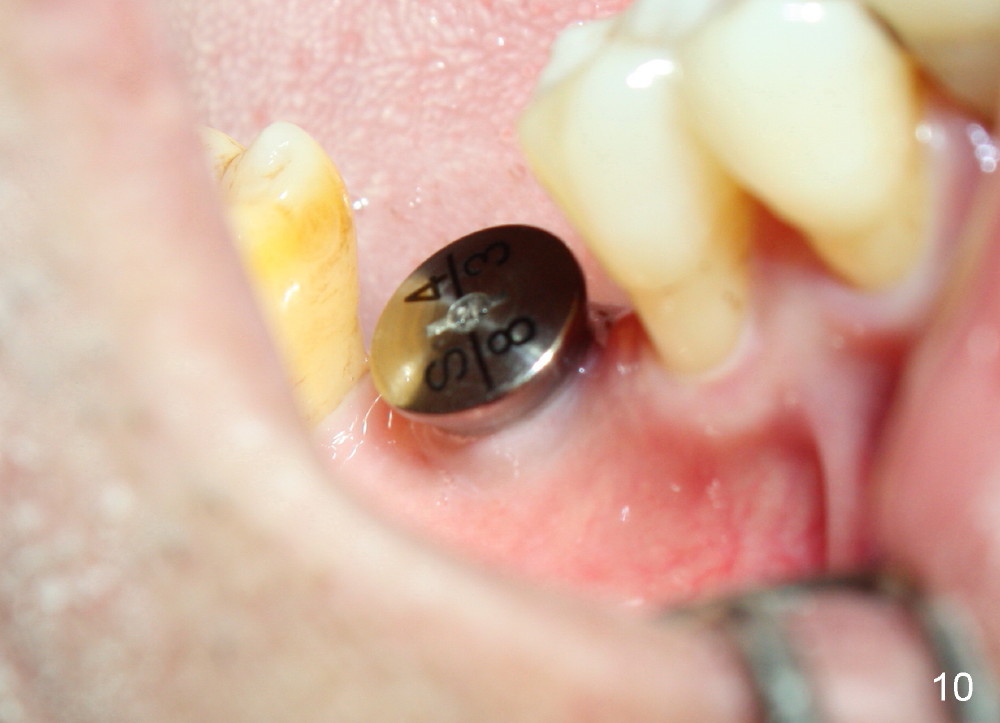

When a positioning pin is placed in the osteotomy with 10 mm deep, the sensor cannot be placed deep enough because of pin interference so no IAC is visible (Fig.4). When the pin is removed and the sensor is placed low enough, IAC is clearly shown, but the osteotomy is barely visible (Fig.5 pink dashed line). With information obtained from pre- (Fig.2,3) and intra- (Fig.4,5) op PA, twelve mm of osteotomy appears to be appropriate. A final implant (5.3x12 mm) is placed with separation from IAC (Fig.6, insertion torque 50 Ncm). A healing abutment is placed (Fig.7,8), which helps retain perio dressing (Fig.9). Two weeks later, the gingiva heals around the abutment (Fig.10). Four months postop, the implant appears to osteointegrate (Fig.11). A cemented abutment is placed (Fig.12). With supragingival margin, oral hygiene is easily maintained (Fig.13). Due to delayed placement, the gingival embrasure is extremely large (*). The issue is much less with immediate implant.